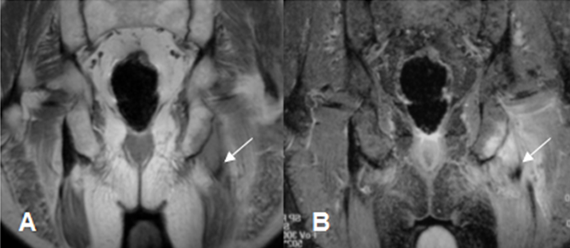

Los casos dudosos se pueden complementar con TAC o RM.

Fig 28. Avulsión.

A: RM coronal en T1 y B: RM coronal en STIR. Cambios inflamatorios sobre la tuberosidad isquiática izquierda por avulsión. Hay retracción en el origen de los isquiotibiales.